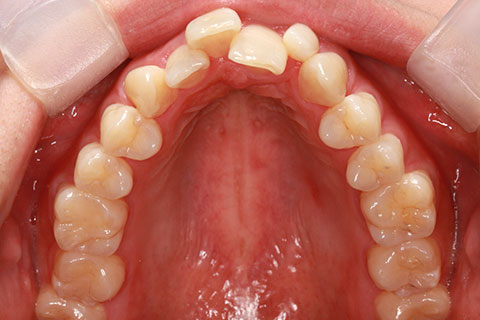

フルリンガル矯正1(上下の歯を舌側矯正で治療)

治療前

治療中

治療後

- 年齢・性別

- 33歳女性

- 治療期間

- 2年0ヶ月

- 抜歯

- 上顎4番抜歯。下顎5番欠損。

- 治療費

- 120万円(税込み)

- フルリンガル矯正

- 治療内容

- 上顎前歯の叢生改善および下顎前歯の空隙閉鎖

- 施術の副作用(リスク)

- 装置が裏側について、目視ができないため、しっかりとブラッシングができているかどうかわかりにくい。